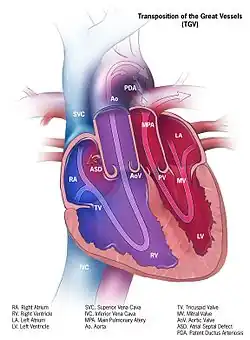

Blood flow diagram of the human heart. Blue components indicate de-oxygenated blood pathways and red components indicate oxygenated blood pathways. | |

Transposition of great arteries

There are two different types of transposition of the great arteries, Dextro-transposition of the great arteries and Levo-transposition of the great arteries, depending on where the chambers and vessels connect. Dextro-transposition happens in about 1 in 4,000 newborns and is when the right ventricle pumps blood into the aorta and deoxygenated blood enters the bloodstream. The temporary procedure is to create an atrial septal defect. A permanent fix is more complicated and involves redirecting the pulmonary return to the right atrium and the systemic return to the left atrium, which is known as the Senning procedure. The Rastelli procedure can also be done by rerouting the left ventricular outflow, dividing the pulmonary trunk, and placing a conduit in between the right ventricle and pulmonary trunk. Levo-transposition happens in about 1 in 13,000 newborns and is characterized by the left ventricle pumping blood into the lungs and the right ventricle pumping the blood into the aorta. This may not produce problems at the beginning, but will eventually due to the different pressures each ventricle uses to pump blood. Switching the left ventricle to be the systemic ventricle and the right ventricle to pump blood into the pulmonary artery can repair levo-transposition.